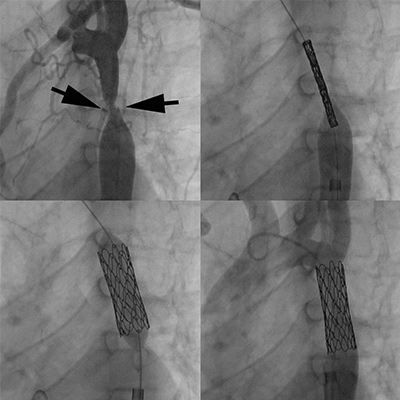

A 15-year old boy was born with a tight coarctation, which was relieved through implantation of a covered stent. (Top left image, in between arrows) documents the narrowing, with positioning of a covered CP stent (top right image). Stent expansion (bottom left) and final angiography documents complete relief of the narrowing with the vessel now wide open (bottom right).